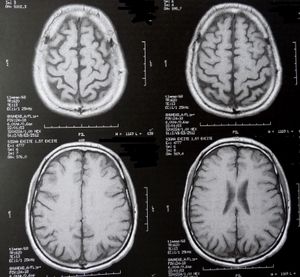

Gehirn-Scans: Tumore sind schwer behandelbar (Foto: pixelio.de, Dieter Schütz) |